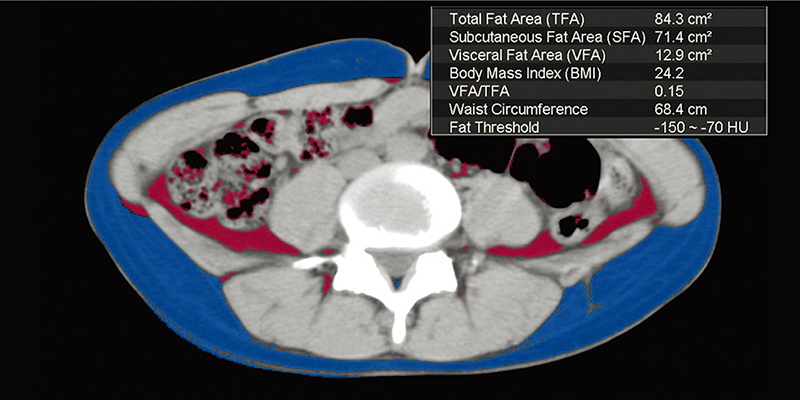

ІНШІ ПАКЕТИ